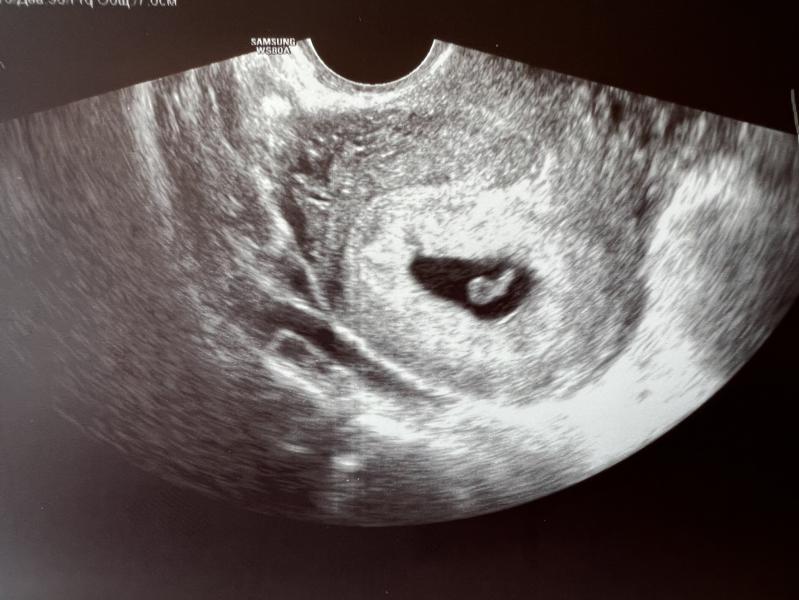

Девочки приветик 🌸На узи сходила срок 6.2 ,все хорошо🤞🌸